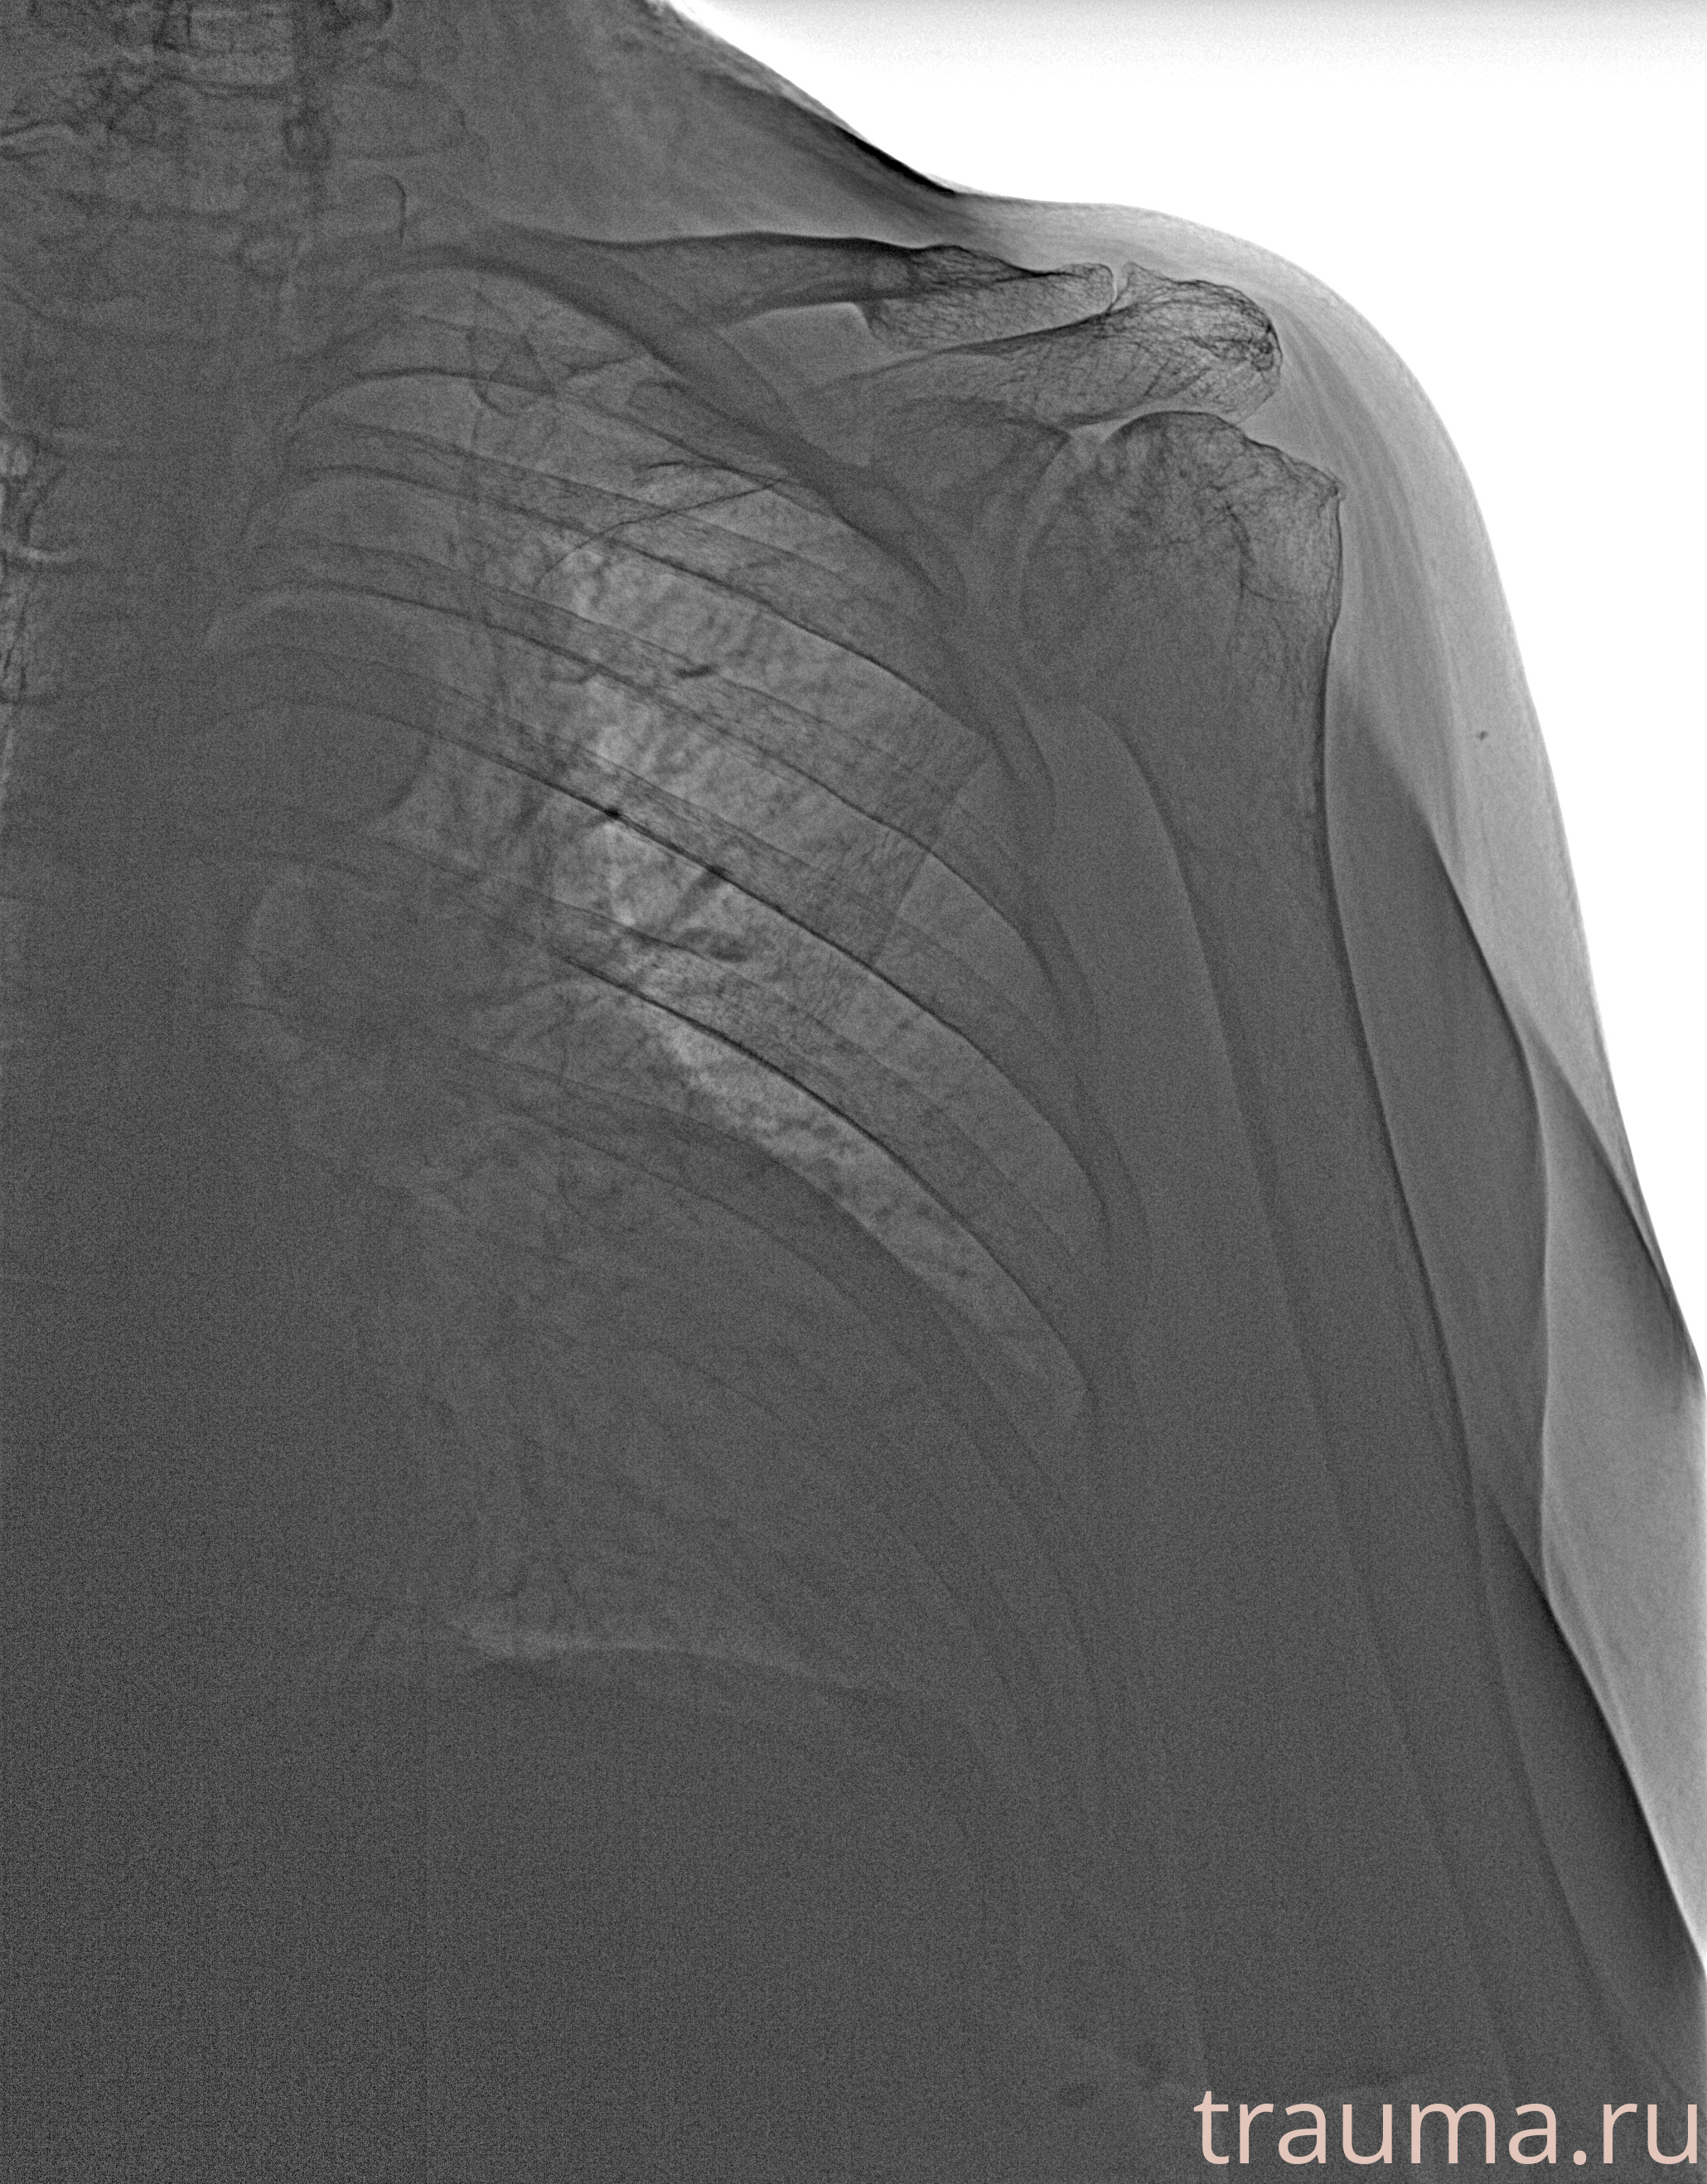

Рентгенограммы

Рентген на дому: по вашему адресу приезжает врач-рентгенолог, травматолог-ортопед с мобильным рентгеновским аппаратом, проводит диагностику травмы или заболевания, делает необходимые рентгенограммы, дает рекомендации по дальнейшему лечению. Получить качественные снимки в домашних условиях возможно благодаря уникальной методике, разработанной МосРентген Центром для института  Склифосовского